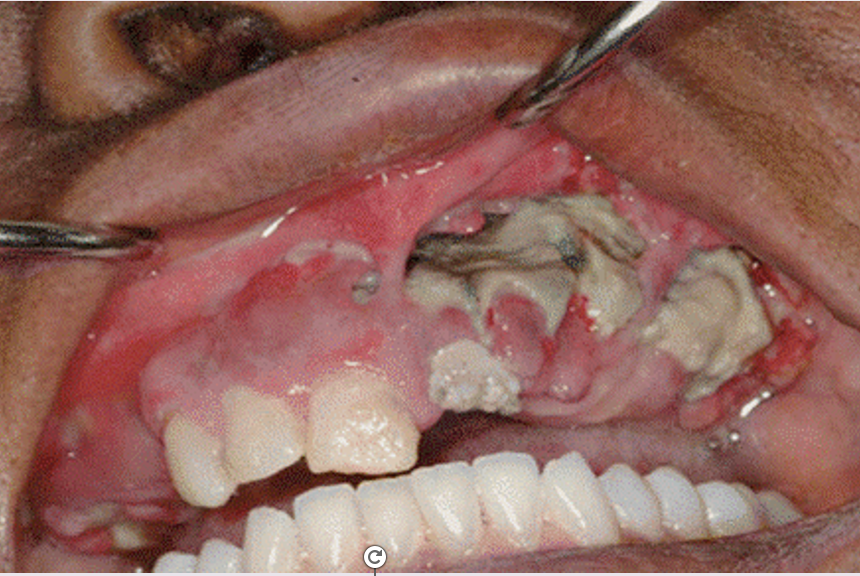

What are some clinical presentations of MRONJ if the patient is symptomatic?

What are the 3 worst case presenations

A

Pain

Swelling

Halitosis

Delayed healing after XLA

Exposed bone & Infection

Numbness of ID nerve

Extra or Intra-oral fistula

Fracture